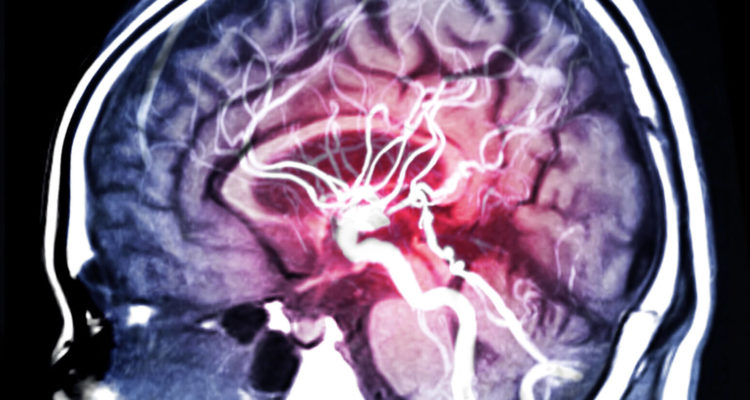

Група крові, відмінна від I, може збільшити ризик інсульту у жінок, які палять і приймають оральні контрацептиви. Такі дані були отримані в рамках попереднього дослідження.

Оральні контрацептиви можуть підвищувати ризик інсульту у деяких жінок, особливо у курців. Через це пацієнткам старше 35 років, які курять, не рекомендується прийом даних препаратів. Попередні дослідження показали, що групи крові з II по IV також можуть збільшувати ризик інсульту.

Вчені виявили, що у жінок, які курили і приймали оральні контрацептиви, ймовірність інсульту була майже в п’ять разів вище, ніж у жінок, які не приймали препарати і не мали шкідливої звички. Група крові, крім I, ще більше збільшила ризик раннього інсульту у жінок, які курили та приймали оральні контрацептиви. Йшлося про підвищення ризику майже в два рази.